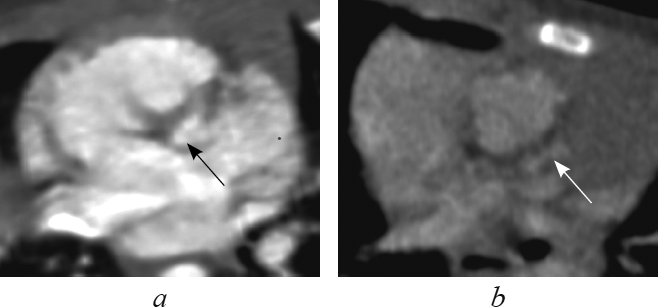

This article contents the results of computed tomography with intravenous bolus contrast media administration data analysis in children with transposition and congenitally corrected transposition of the great arteries with the consequental performing of the multiplanar heart-axis-oriented reformations. Among 148 examined children transposition of great arteries was detected in 13 patients (9 boys and 4 girls aged 1-144 day of life); congenitally corrected transposition was found in 4 cases of children aged from 6 months to 15 years and 6 months (2 boys and 2 girls). In this article comprehensive anatomical criteria of each heart chamber morphology are presented and reformations where these criteria can be seen are shown. Also in the article is given comparative characterization of heart and great arteries structures in transposition and congenitally corrected transposition in every certain heart-axis-oriented reformation. By the results of consequently performed heart-axis-oriented reformations data analysis the peculiar anatomical signs of transposition and congenitally corrected transposition are determined. The results of data analysis show that from the list of offered reformations the peculiar anatomical signs of both kinds of transposition are significantly determined in long-axis of right ventricle inflow tract reformation, left heart chambers reformation, supply ventricle division reformation, short-axis reformation at the level of great arteries. Computed tomographic angiocardiography heart-axis-oriented multiplanar reformations permit full and correct assessment of heart and main vessels, which is important for planning of surgical treatment in congenital heart diseases.